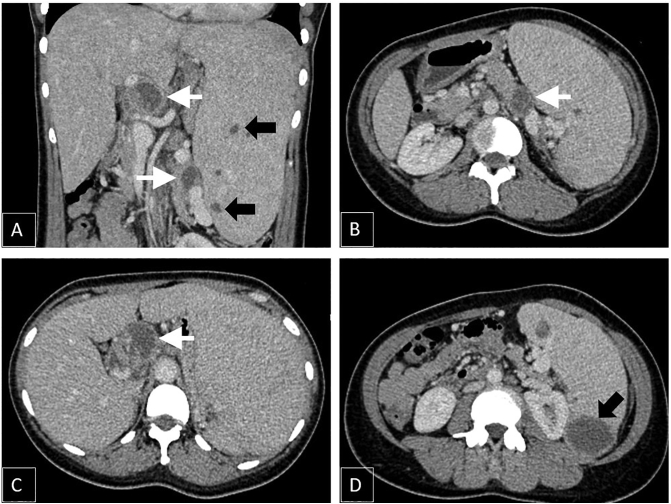

From the physical examination, the prominent finding was isolated enlargement of the patient's spleen (Schuffner IV). Laboratory examination showed leucocytosis and thrombocytosis with positive Interferon Gamma Release Assays (IGRA) test. Anti-Human Immunodeficiency Virus (HIV) test was negative. There were no signs of TB infection from the chest x-ray examination. The CT scan examination revealed spleen enlargement with multiple rim-enhanced cystic lesions mostly within inferior pole parenchyma. There were also cystic lesions within the body and tail of the pancreas and lymph node enlargement of the perihilar and paraaortic region with central necrosis (Fig. 1).

Fig. 1.

Contrast-enhanced CT (axial and coronal) images A-D showing multiple rim-enhanced cystic lesions within spleen parenchyma (black arrow) with multiple lymph node enlargement with central necrosis (white arrow).